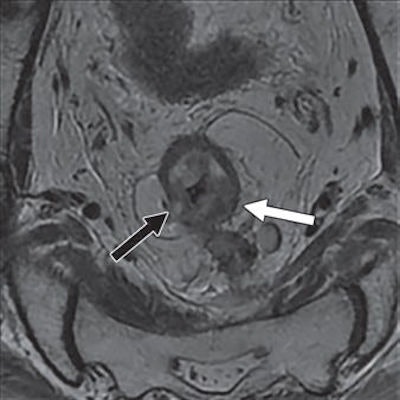

Jia and colleagues found that MRI correctly predicted tumor regression grade in 34 cases (59.6%), while the modality overstaged six patients (10.5%). Of those cases, three patients (50%) had severe edema of the mucosa and submucosa adjacent to the tumor, which was misinterpreted as residual tumor. In two patients (33.3%), the muscular layer next to fibrotic area appeared as intermediate signal intensity on T2-weighted images and was misinterpreted as residual tumor. The sixth patient was misdiagnosed with a diagnosis of mucinous adenocarcinoma.

The researchers also found that fibrosis "could manifest as a shape and signal intensity similar to the shape and signal intensity of invaded vessels that shrank after treatment. This result was especially evident in vessels with a diameter smaller than 3 mm.

Conversely, MRI understaged seven patients' (12.3%) tumor regression grades. In all cases, the patients had their post-treatment tumor regression grade of 3 mistakenly classified as grade 2 due to fibrosis in the tumor area.